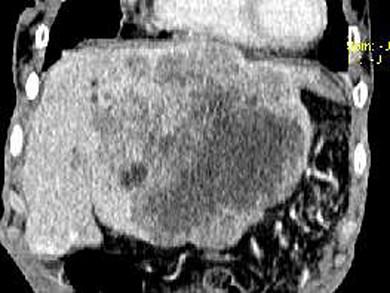

问题 女,73岁,中上腹痛一月余,患者黄疸、消瘦,CT检查如下图,最可能的诊断是 ( )

选项 A、肝淋巴管瘤 B、肝胆管细胞癌 C、巨块型肝癌 D、肝血管瘤 E、肝脓肿

答案 C